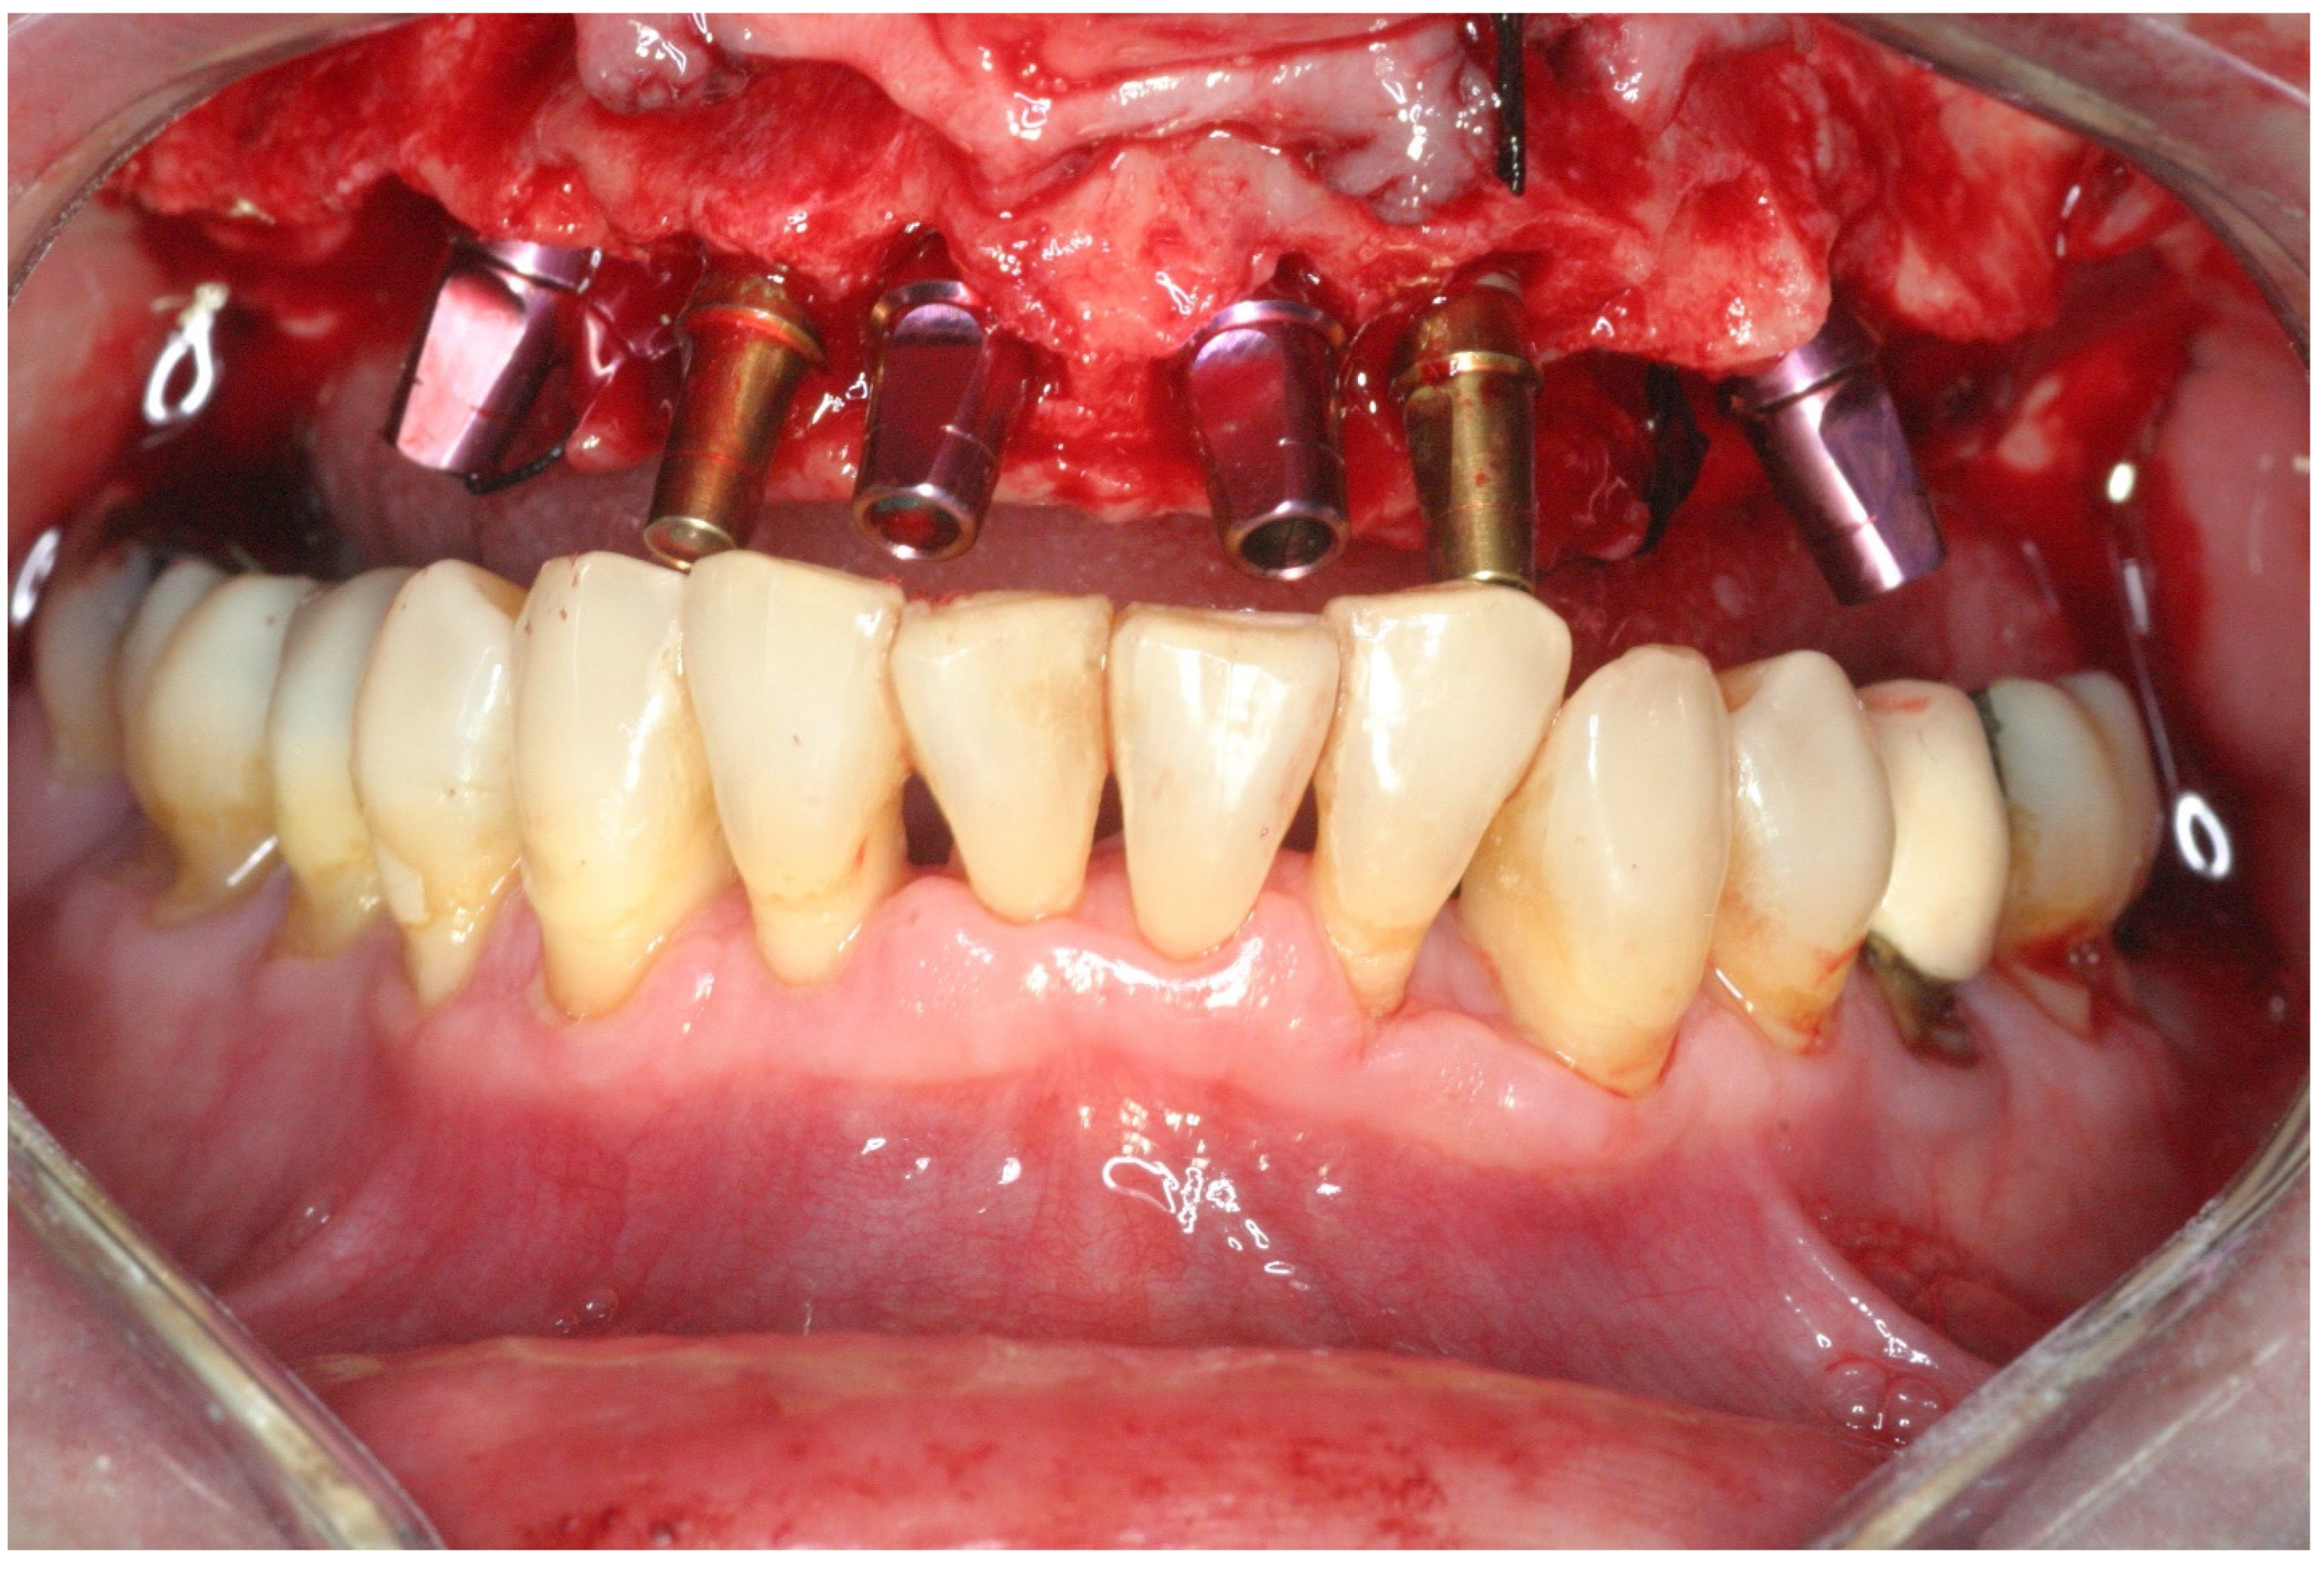

2.2. Surgical Treatment

2.3. Prosthetic Protocol